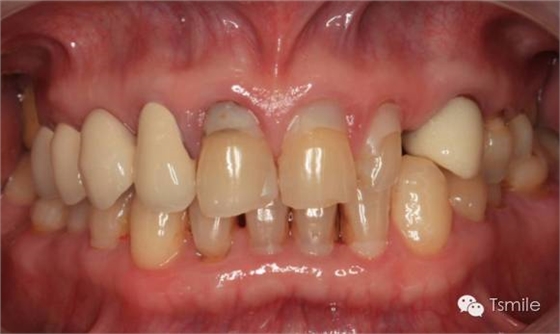

牙列重度磨耗的患者,特別是全牙列重度磨耗的患者,其口腔美觀和功能都受到了嚴(yán)重影響?;颊卟粌H需要口腔美學(xué)重建,還需要口腔功能的重建。

例如面對一個牙列重度磨耗的美學(xué)修復(fù)患者,我們首先根據(jù)患者主訴和美學(xué)檢查形成美學(xué)設(shè)計,然后通過數(shù)碼圖像表達(dá)美學(xué)設(shè)計思想,制作診斷蠟型,口內(nèi)制作診斷飾面,更加真實(shí)地表達(dá)美學(xué)設(shè)計。根據(jù)患者的要求和口內(nèi)試戴情況調(diào)改診斷飾面,最終確定美學(xué)修復(fù)設(shè)計,即最終修復(fù)體的各種美學(xué)參數(shù)。接下來就是美學(xué)實(shí)現(xiàn)過程,在診斷飾面上進(jìn)行精確地牙體預(yù)備,制取印模和工作模型,技師按照最終診斷飾面的形態(tài)、大小和排列制作最終美學(xué)修復(fù)體,最后完成修復(fù)體粘接。